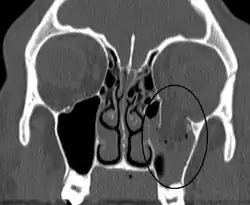

| An orbital blowout fracture of the floor of the left orbit. | |

Thin cut (2-3mm) CT scan with axial and coronal view is the optimal study of choice for orbital fractures.[16][17]

Plain radiographs, on the other hand, do not have the sensitively capture blowout fractures.[18] On Water's view radiograph, polypoid mass can be observed hanging from the floor into the maxillary antrum, classically known as teardrop sign, as it usually is in shape of a teardrop. This polypoid mass consists of herniated orbital contents, periorbital fat and inferior rectus muscle. The affected sinus is partially opacified on radiograph. Air-fluid level in maxillary sinus may sometimes be seen due to presence of blood. Lucency in orbits (on a radiograph) usually indicate orbital emphysema.[4]